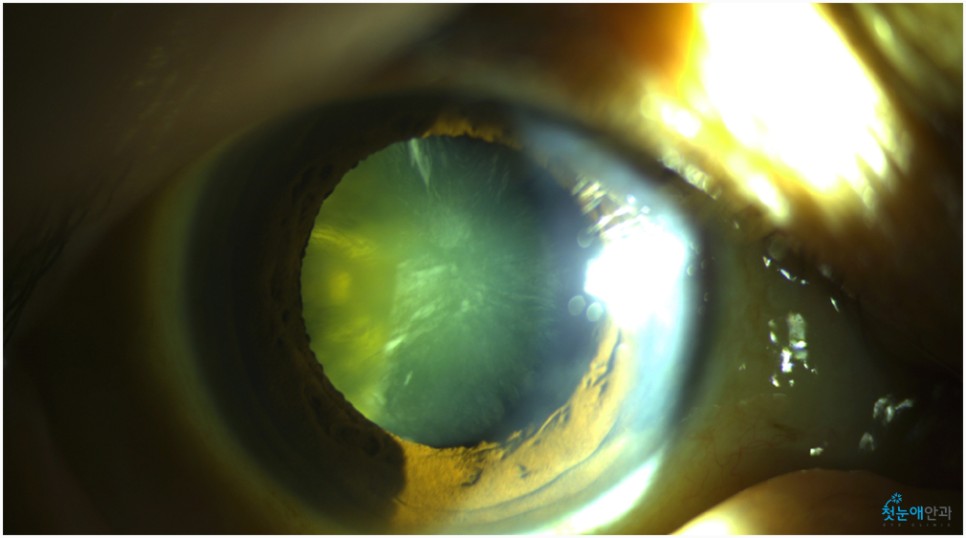

노안 수술 안과에 내원하셨을 때 오른쪽 눈이 잘 보이지 않는다고 말씀하셨습니다.이에 첫눈 애안과 장비를 통해 조사한 결과 이미 백내장 진행이 상당하고 눈 밑 망막 관찰이 어려울 정도로 흐릿한 상태였습니다.

눈이 침침해서 잘 보이지 않았던 것은 올해 초부터라고 말씀하셨습니다.진단 결과 백내장 B) N5CO(+++) PSC(+++) 단계에 해당되며 이는 매우 심한 정도여서 예전에는 맑은 수정체였으나 지금은 혼탁하고 진한 갈색으로 바뀌었습니다.참고로 백내장 초기라면 약물 사용으로 진행을 늦출 수 있었을 것 같은데, 노안수술안과를 방문해주신 환자들은 너무 많은 진행이 있었기 때문에 수술이 필요했습니다.

백내장이 상당히 진행되면 수정체가 흐려져 눈 아래의 망막 관찰이 어렵습니다.때문에 사진을 찍어 검사해봐야 하는데 위와 같이 흐릿한 사진이 찍혀 사실상 망막 관찰이 어렵습니다.뿐만 아니라 심한 백내장은 부분마취 수술 진행이 어려워 안구마취나 전신마취로 수술하거나 종합병원으로 전환해 수술해야 합니다.뿌옇게 변했는데도 그냥 놔두면 위 사진처럼 더 심해져 시력이 저하되는 상황까지 이어지게 됩니다.